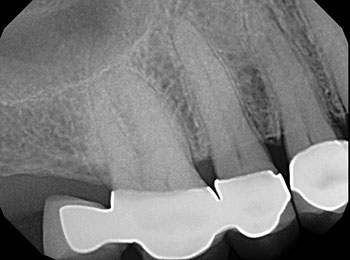

Root canal treatment is a procedure in which the nerve or pulp of the tooth is removed. Patients can need root canals for many different reasons. Is is most common when there is either inflammation or infection of the nerve of the tooth. Sometime a root canal is simply necessary due to lack of tooth structure to restore the tooth. During a root canal, the dentist will isolate the area and carefully clean, shape, disinfect, and fill the canals of the roots to seal the space. Most often we will recommend a crown to help strengthen the tooth and prevent it from fracturing.

Before root canal

After root canal